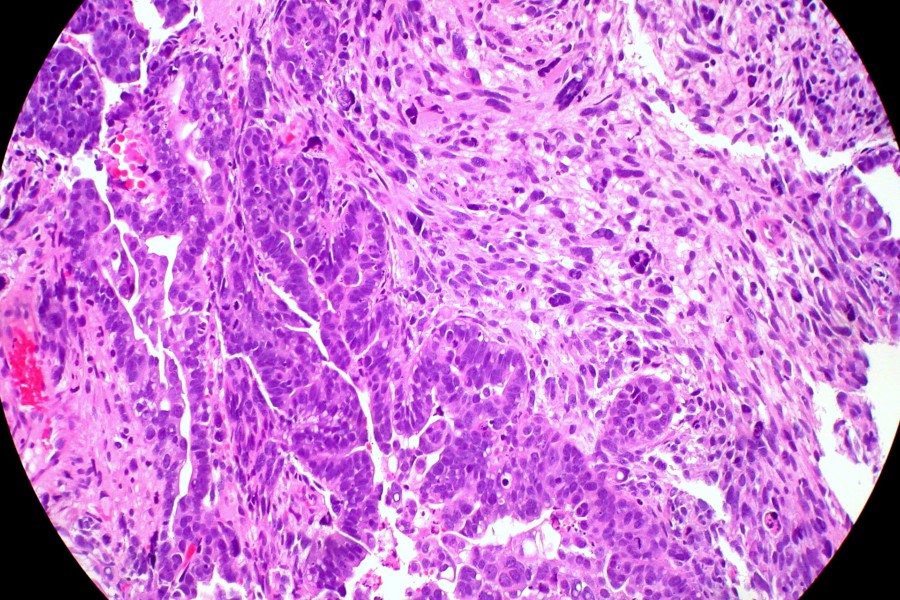

Investigación sobre el cáncer de endometrio: un avance prometedor

Un reciente estudio sugiere que la inhibición de la proteína receptora CXCR6, asociada a la molécula CXCL16, podría ser clave para frenar la metástasis en pacientes con cáncer de endometrio. Esta investigación ha sido liderada por un equipo del Institut de Recerca Biomèdica de Lleida (IRBLleida) y la Universitat de Lleida (UdL), y los hallazgos han sido publicados en la revista Cell Death & Disease.

La citocina CXCL16 es una de las sustancias que las células cancerosas liberan al entorno, formando parte del secretoma. Este proceso facilita el crecimiento tumoral, aumenta la capacidad invasiva y genera una mayor resistencia a los tratamientos convencionales. Comprender este mecanismo molecular podría allanar el camino hacia terapias más efectivas.

El equipo investigador ha utilizado modelos animales y muestras de tejido humano para identificar el mencionado mecanismo molecular en células afectadas por la pérdida del gen ARID1A. Los resultados indican que inhibir la proteína CXCR6 o su receptor interrumpe las interacciones patogénicas, dificultando así la migración celular y reduciendo la carga metastática. La primera autora del estudio, Cristina Megino Luque, quien realizó su tesis doctoral en la UdL y actualmente trabaja en el Tisch Cancer Institute de Nueva York, considera que estos hallazgos sugieren una nueva estrategia terapéutica para aquellos pacientes con formas más avanzadas o agresivas de esta enfermedad.